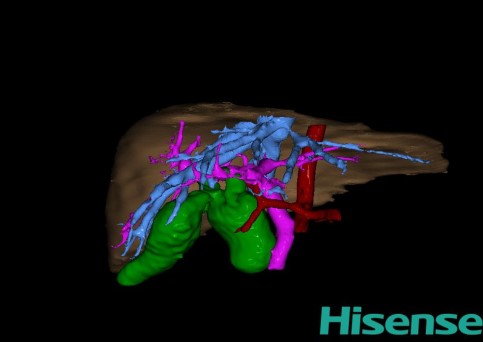

10、三维重建虚拟肝脏、胆道显像技术

三维虚拟肝脏技术是在二维影像学资料如CT等图像的基础上,通过三维重组软件和工具,比如青岛大学附属医院与海信医疗集团联合自主研发的海信计算机辅助手术系统(Hisense Computer Assisted Surgery,Hisense CAS),目前已投入临床并指导实际应用,利用该类系统对二维影像学的数据资料进行三维立体分析,重组形成立体的、有空间结构的、虚拟的肝脏三维图像。这项技术较传统的二维平面成像技术,有着明显的优势,3D虚拟肝脏技术可以构造出一个虚拟的、可视化的肝脏模型。通过对这种模型的观察,可以很容易地分辨出肝脏器官的组织结构、解剖特点,直观研究肝外胆总管的形态差异,明确肝内胆管的形态、走形、是否合并扩张、狭窄及结石,胰胆管合流的形态及共同通道内是否有狭窄、扩张和结石等病变情况,预先规划处理可能合并存在的肝内胆管扩张、狭窄或其他复杂胆道畸形,清晰地显示肝内脉管系统,包括门静脉、肝动脉及肝静脉的走行、分支,并可多角度、全方位观察病变胆道与其周围重要血管尤其是伴行的门静脉之间的解剖关系,大大提高了外科医师在术前对肝脏内部各管道结构及其变异判断的精确性和可靠性,精准地对病变进行判断和评估,还可根据患者自身的病变特点,制定出合理、个体化的手术方案,最大限度地降低术中和术后并发症发生率,并术中导航实时指导手术,提高手术的精准性和成功率。

图11:先天性胆管扩张症梭状型三维重建虚拟肝脏、胆道显像

a 图为术前二维CT扫描图像,箭头指示肝内胆管扩张;b 图为CT经多平面重组技术(MPR)所得的重建图像,可粗略地判断病变胆管的位置;c 图示术前Hisense CAS三维重建清晰显示胆管的病理形态及其与肝内三套血管系统的解剖关系;d 图示胆道系统与其伴行的门静脉系统的空间解剖关系;e 图为胆道系统立体形态,箭头处指示迷走胆管,源自肝脏直接汇入胆总管。术前规划先将迷走胆管与肝总管吻合成形,再行肝总管空肠Roux-en-Y吻合术。